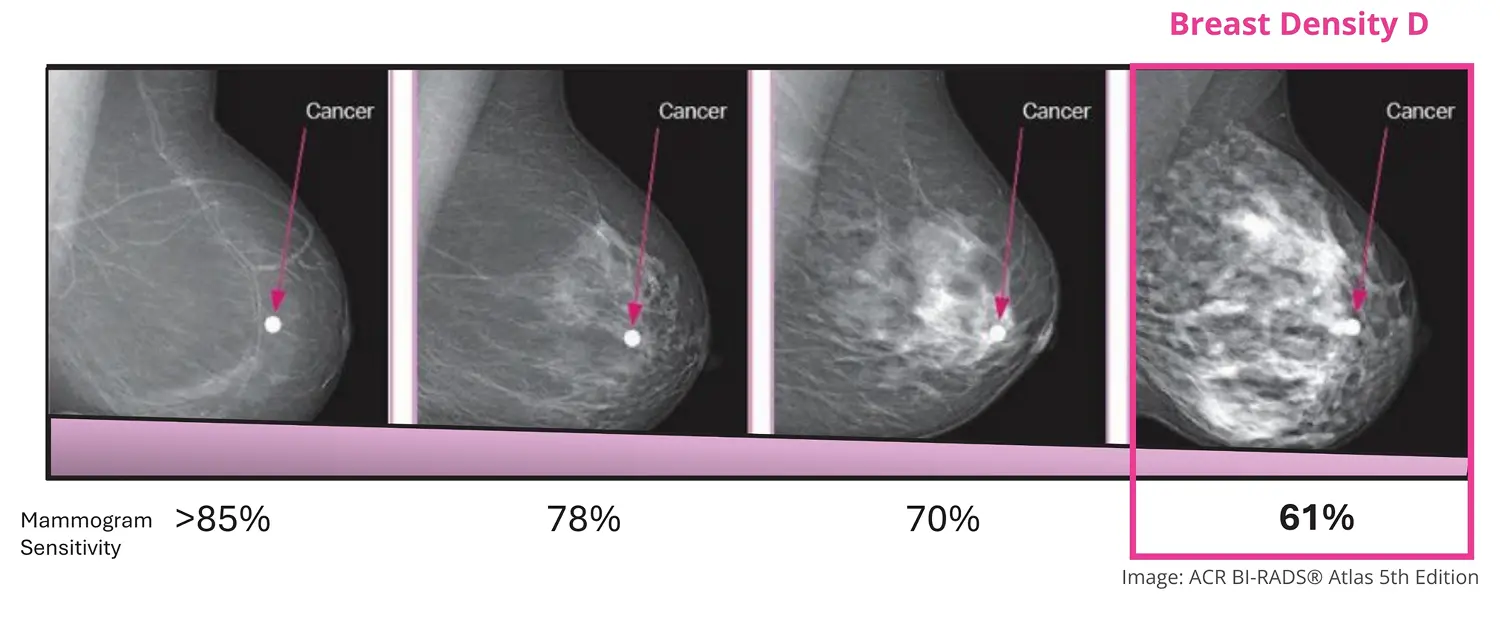

Dense breasts can hide cancers because dense tissue and breast cancers both appear white on a mammogram. The higher the density, the harder it can be to see cancer.1,2,4,6

The higher the level of breast density, the harder it can be to detect breast cancer on a mammogram.1,2,4,6

Mammograms save lives7 – and only a mammogram can tell you if you have dense breasts.4,6 In women with dense breasts, mammogram sensitivity can be reduced.1,2,4

Mammogram sensitivity decreases as breast density increases22>

Sensitivity is a measure of how good a mammogram is at finding breast cancers when they are there. A high sensitivity means the test picks up most cancers and misses very few. A lower sensitivity means the test may miss some cancers — even though they are present.